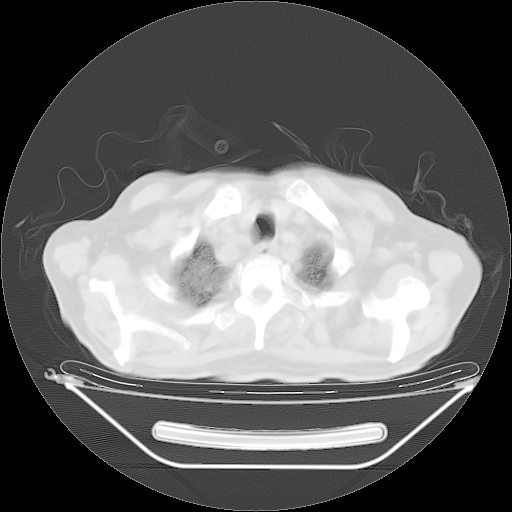

今天复查肺部CT,发现双肺广泛磨玻璃样改变。所以我把3月19日和5月9日相隔50天的肺部CT上传。请大家会诊。

2009年3月19日肺部CT片。

2009年3月19日肺部CT

大致读了系列胸部CT:纵隔窗无明显异常,肺窗:从4、27至今:主要是双肺中下野外带可见毛玻璃样改变,目前处于急性肺泡炎阶段,至于原因考虑1、结替组织或胶原血管性疾病所致?2、恶性疾病如恶组在肺部所致的表现或细支气管肺泡癌?3、药物或其它原因如肺蛋白沉着症所致肺泡炎目前不太可能?总之,明天就去请我院的呼吸科、感染科、血液科和临免专家会诊哈。